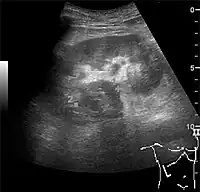

The hydronephrosis is typically graded visually and can be divided into five categories going from a slight expansion of the renal pelvis to end-stage hydronephrosis with cortical thinning (Figure 15). The evaluation of hydronephrosis can also include measures of calyces at the level of the neck in the longitudinal scan plane, of the dilated renal pelvis in the transverse scan plane and the cortical thickness, as explained previously (Figure 16 and Figure 17).[1]

Figure 15. End-stage hydronephrosis with cortical thinning. Measurement of pelvic dilatation on the US image is illustrated by ‘+’ and a dashed line.[1] Figure 16. Hydronephrosis with dilated anechoic pelvis and calyces, along with cortical atrophy. The width of a calyx is measured on the US image in the longitudinal scan plane, and illustrated by ‘+’ and a dashed line.[1]

Figure 16. Hydronephrosis with dilated anechoic pelvis and calyces, along with cortical atrophy. The width of a calyx is measured on the US image in the longitudinal scan plane, and illustrated by ‘+’ and a dashed line.[1] Figure 17. Same patient as in Figure 16 with measurement of the pelvis dilation in the transverse scan plane illustrated on the US image with ‘+’ and a dashed line.[1]